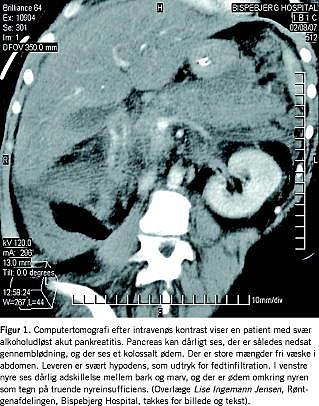

Alkohol metaboliseres i et vist omfang i pancreas, hvor det reducerer blodgennemstrømningen og øger dannelsen af frie oxygenradikaler [5]. Derved øger alkohol risikoen for udvikling af akut inflammation i pancreas (Figur 1). Alkohol alene kan dog ikke forklare, hvorfor sygdomsprocessen begynder. Således får kun ca. 10% af patienterne med svært alkoholmisbrug klinisk erkendelig inflammation i pancreas [5].